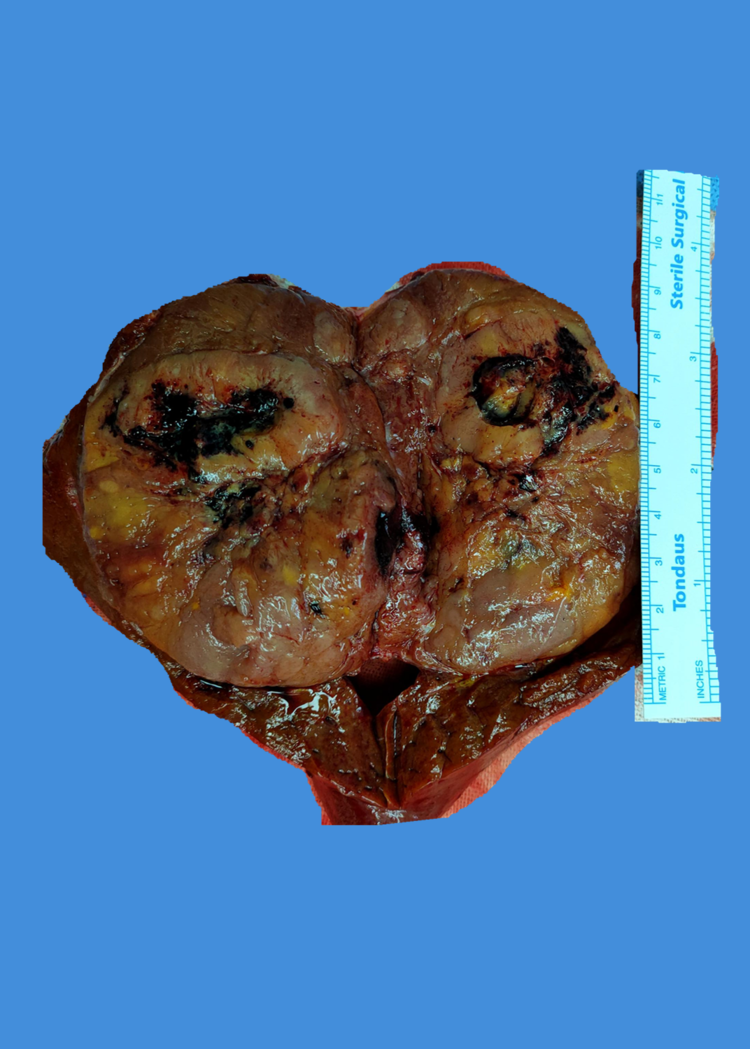

术中照片

术后病理报告